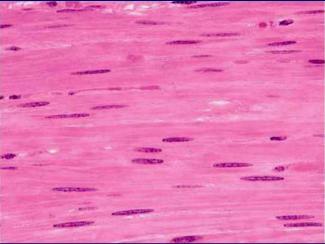

Músculo liso